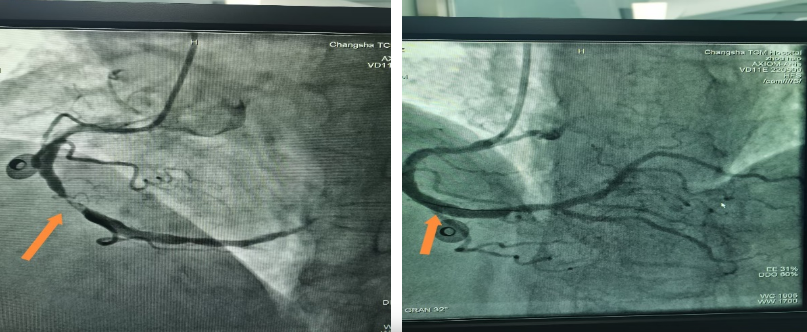

时间就是心肌,时间就是生命。接到通知,医院立即启动胸痛中心应急预案。患者抵达医院时,仍反复胸痛不止。在与家属进行简短有效沟通后,患者被送入介入治疗室。术中造影显示,患者最重要的供血血管之一——右冠中段完全闭塞,情况十万火急。

虽是除夕,医护团队没有丝毫懈怠。曾向辉副主任、丁赛良副主任医师与导管室护士、技师默契配合,导丝迅速通过病变部位,一枚支架精准植入……堵塞的血管被成功开通。从患者进入医院到血管开通,全程仅用时60分钟,比国际标准的90分钟快了整整半个小时。这背后,是医院胸痛中心区域协同救治体系高效运转的体现,更是医护团队过硬专业素养的证明。